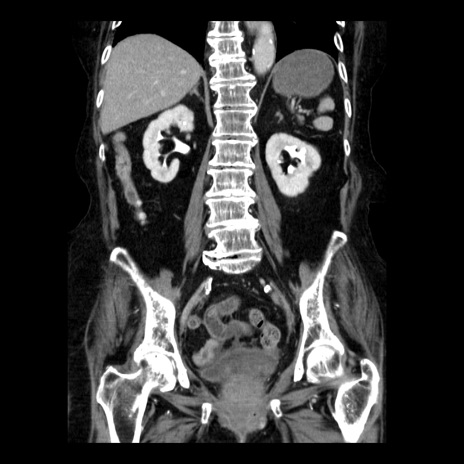

症例14(冠状断像)

【症例】 90歳代女性

【主訴】 腹痛・嘔吐

【現病歴】今朝から左側腹部痛を認めた。 経過観察していたが、嘔吐を認めたため来院。

【既往歴】 子宮癌術後

【身体所見】 意識清明、BP 127/54mmHg、P 98bpm Sp02 95%(RA)、BT 35.8°C、腹部平坦・軟腸ぜん動音聴取良好、右下腹部圧痛(+) 反跳痛なし

【データ】WBC 9800、CRP 0.46